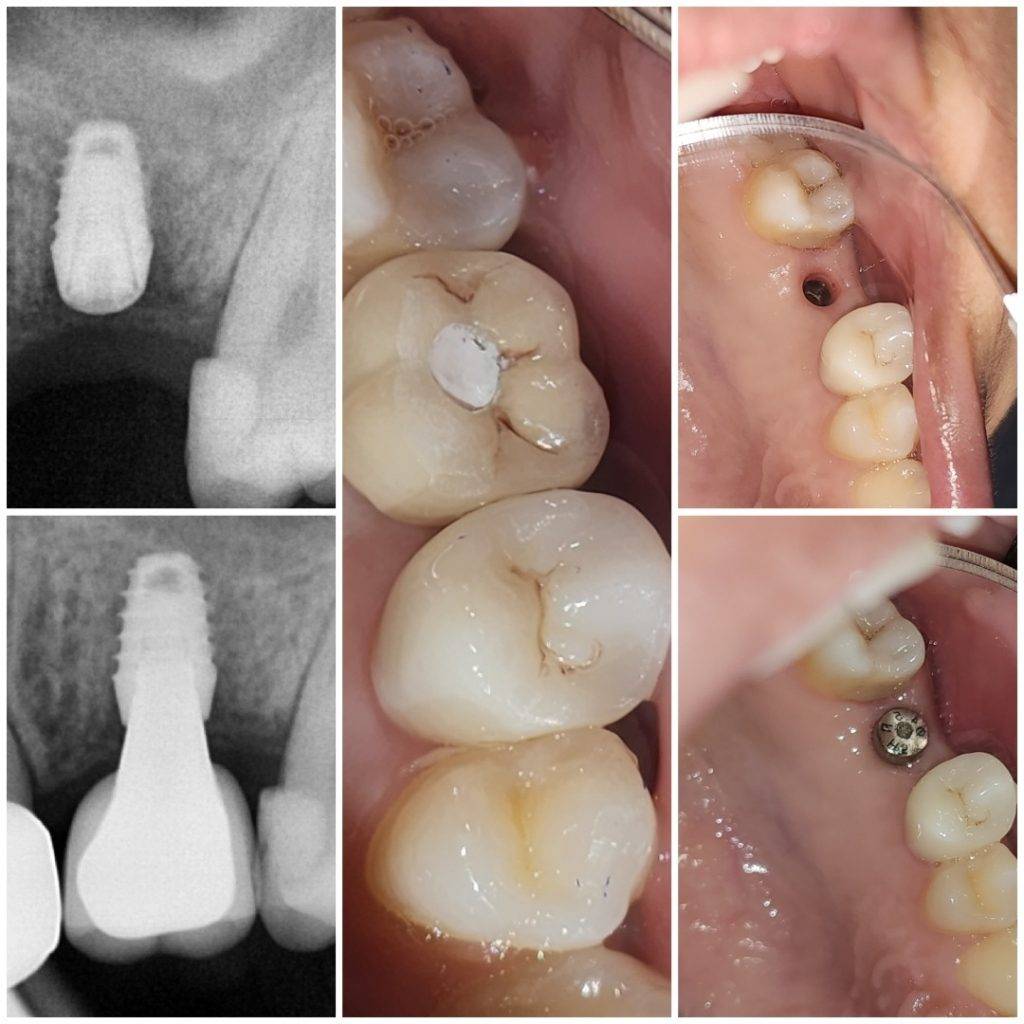

Treatment Gallery

At The Dental Tree & Facial Cosmetic Centre, the centre of our universe is our patients. Satisfaction of our patients has always been our top priority and always will be. This is the reason why we are the Best Dental Clinic in Indirapuram and why we do what we do.

Our Gallery